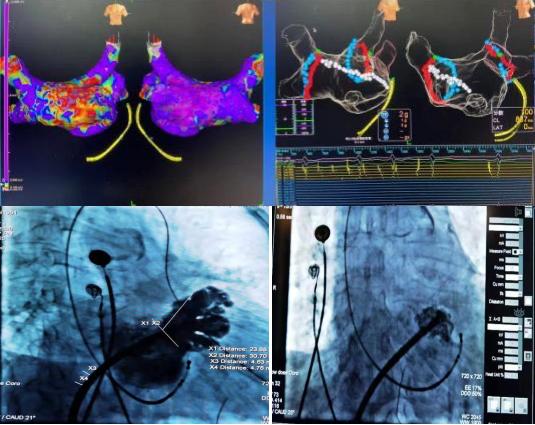

78岁高龄的杜奶奶,受到房颤疾病困扰多年,从宝鸡慕名来到我院。经我科高胜利主任、贺新荣责任总医师及徐云鹏主治医生的详细检查与谨慎的决策,同时在心血管病院吴栋梁院长、张玉顺教授和电生理同仁的协助下,成功地进行了一站式手术。该手术分两部分进行,首先是行房颤射频消融术:房颤射频消融手术可最大限度地使患者恢复窦性心律(正常心律);第二部分是行左心耳封堵术:左心耳封堵术是目前全球预防房颤患者卒中的治疗新趋势,它能有效减少病人的病死率、致残率,同时减少出血的发生。两种手术一站式结合,“一消一封”,“一劳永逸”。手术过程顺利,术后患者转复为窦性心律,左心耳封堵伞完全展开,造影显示无残余分流。患者各项生命体征平稳,顺利返回病房。在主管护师赵燕子的全程指导下,护理团队从患者卧位-饮食-运动-心理进行全方位的护理。新年的第4天,杜奶奶恢复情况良好,顺利出院。她笑着说:“我好了,我好了,太谢谢你们了”!